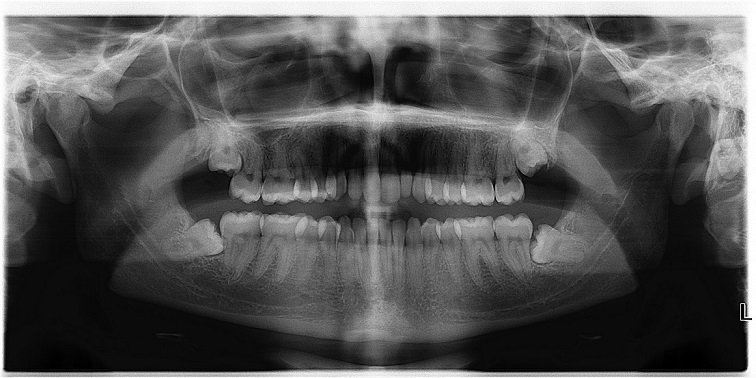

- Cắt nang chân răng, Phẫu thuật răng khôn. Đây là loại phẫu thuật thường gặp nhất và cũng thường xuyên nhận được nhiều sự quan tâm của khách hàng nhất.

Răng khôn là răng mọc sau cùng trên cung hàm khi đã trưởng thành nên thường bị thiếu chỗ gây mọc lệch, kẹt ...Nếu răng mọc thẳng,khớp cắn tốt với răng trên và không gây bất kỳ một biến chứng nào thì không cần nhổ nhưng trường hợp này chỉ chiếm một tỷ lệ rất nhỏ.

Răng mọc lệch: có thể lệch gần, trong ngoài, xa…nhưng thường gặp nhất là răng khôn dưới lệch gần.

Máy chụp film Cone Beam CT để chẩn đoán và biết được chính xác các mốc giải phẫu quan trọng.